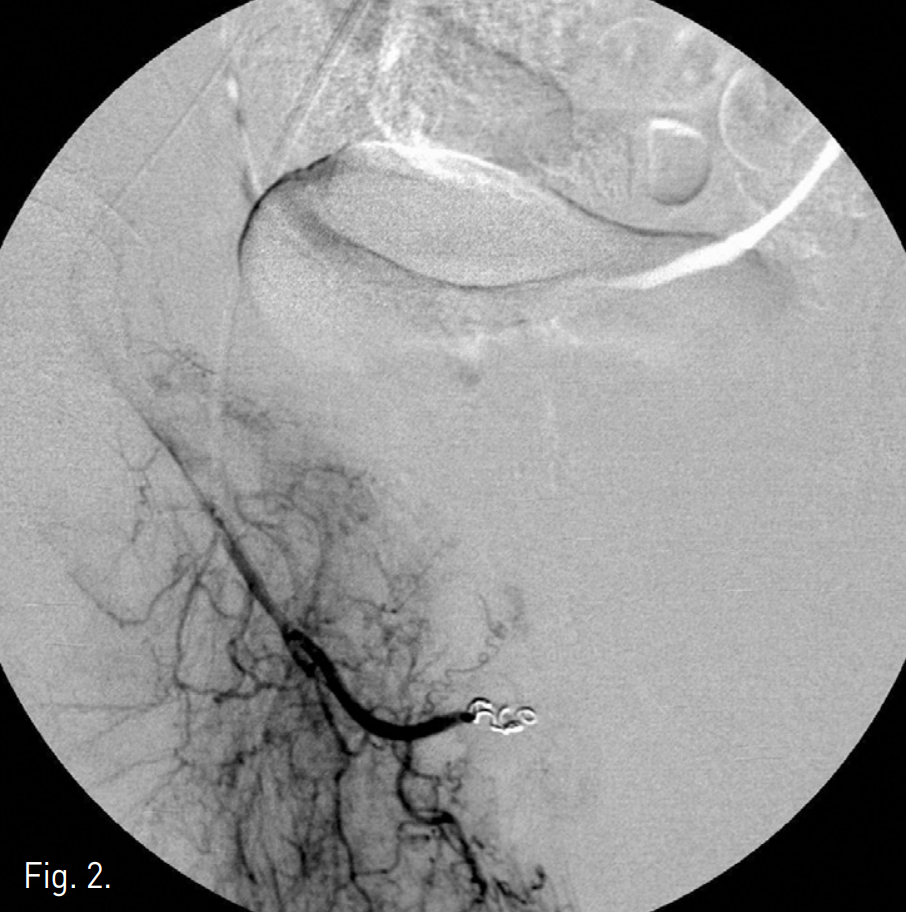

Fig. 2

Right internal iliac angiogram after embolization using coils shows complete occlusion of arterio-cavernous fistula.